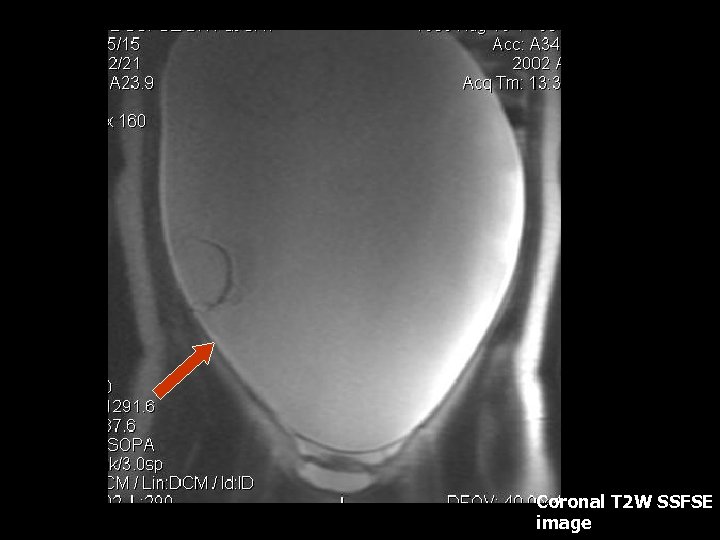

Perirectal Abscess • MRI findings: Non-specific – focal fluid collection with rim enhancement after IV contrast administration(7).

Axial SSFSE T 2 W image